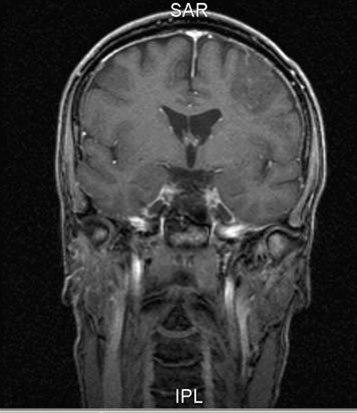

Oligodendrogliom, koronart snitt

Gjengitt med tillatelse av Radiologisk avdeling, Universitetssykehuset Nord-Norge